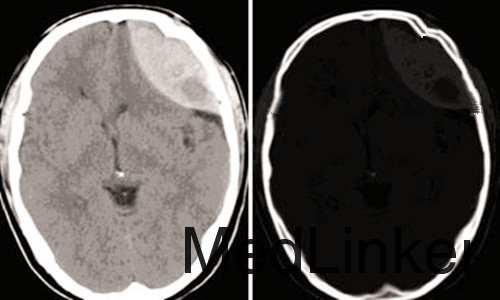

主诉:外伤致伤头部,昏迷、留血1小时。 病史:41岁男性患者,1小时前因打球不慎跌伤致伤头部,头面部多处血迹,当时出现昏迷不醒,无恶心、呕吐,无四肢抽搐,无大小便失禁,左侧瞳孔明显散大,直径约4mm。急诊行头颅CT检查示:左侧额部硬膜外出血合并头皮血肿,广泛颅骨骨折。住院观察病情,进一步治疗。

查体:T 36.5°C P:82次/分 R:20次/分 BP:142/80mmHg。发育正常,营养中等,被动体位,急性面容,表情痛苦,昏迷,查体不配合。左侧额部巨大肿块,左侧瞳孔散大,左侧对光反射迟钝,双肺呼吸音略粗,未闻及干湿性啰音。GCS8分,左顶部可触及一个手掌大小的头皮血肿,口鼻腔可见血性分泌物。 辅查:头颅CT:左额部硬膜外出血,广泛颅骨骨折。

诊断:1.左额部硬膜外血肿;2.左额部头皮血肿;3.左侧额部颅骨骨折 治疗:完善相关检查,积极做好术前准备,拟急诊行“去骨瓣减压术+硬膜外血肿清除术”。